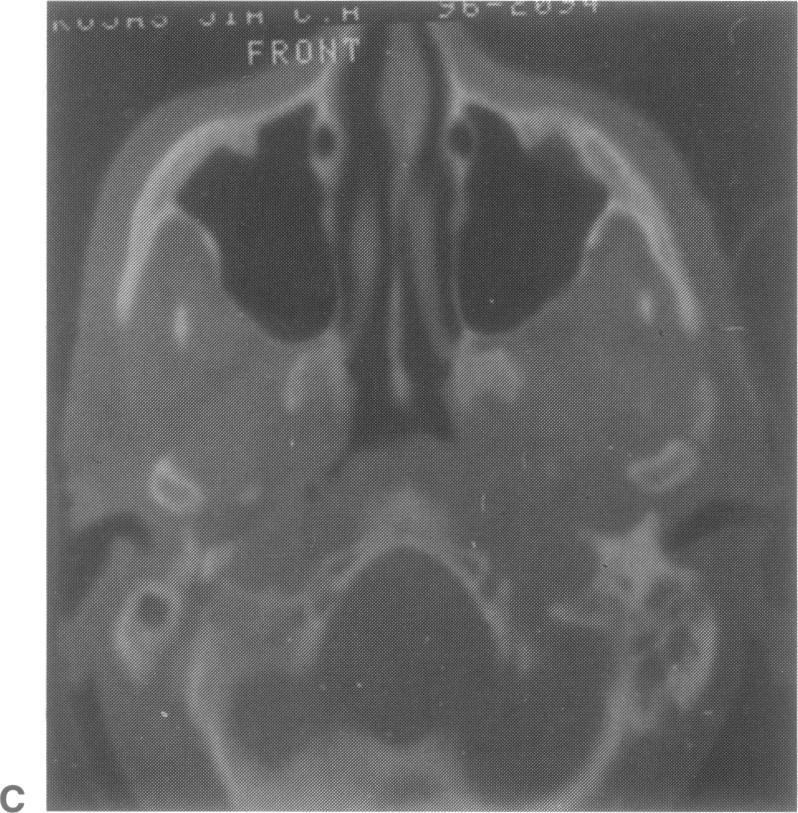

A case of a basal middle fossa giant cell tumor occurring in a 46-year-old man is described. The lesion appeared at the computed tomography (CT) scan examination as an hypodense mass with a peripheral "ring-like" enhancement, and no evident erosion of the skull base. The tumor, which infiltrated the basal temporal parenchyma, was removed via a temporal transzygomatic craniotomy, and extensive drilling of the petrous bone. Despite the occurrence, of significant postoperative complications, the patient ultimately showed a good clinical outcome, with no signs of recurrence at the 1-year follow-up CT scanning. The clinical and diageostic aspects and the management policy, of this rare lesion are discussed.

本文描述了一例发生在一名46岁男性的颅中窝底巨细胞瘤。在计算机断层扫描(CT)检查中,该病变表现为低密度肿块,周边有“环状”强化,且颅底无明显骨质侵蚀。肿瘤侵犯颞叶底部实质,通过颞部经颧弓开颅术及广泛磨除岩骨将其切除。尽管术后出现了严重并发症,但患者最终临床效果良好,术后1年的CT扫描未见复发迹象。本文还讨论了这种罕见病变的临床和诊断方面以及治疗策略。